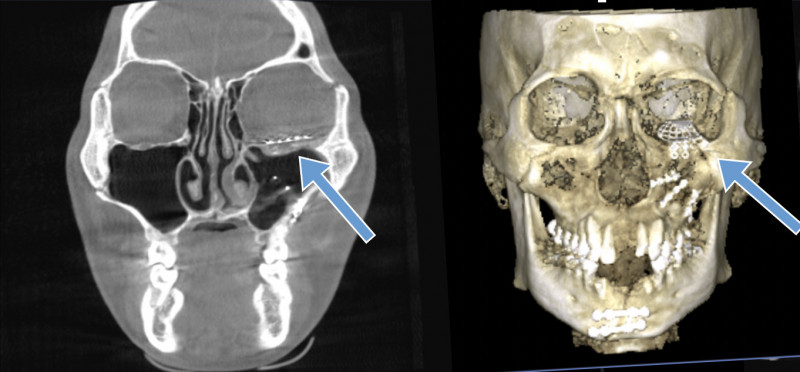

陳先生車禍造成全臉複雜性顏面骨折,上顎、眼底、鼻樑骨、鼻竇、顴骨骨折,下顎、齒槽骨有10多處也骨折缺損,傷勢嚴重。台中榮總口腔顎面外科醫師連凱華指出,傷患的眼球下直肌也被骨折碎片夾住,導致眼球下陷,骨折嚴重也造成面部過度腫脹,加上心眼反射,有致命危機,必須緊急手術。

由於陳先生眼眶骨骨折碎裂嚴重,連凱華再以未骨折的右側眼眶鏡像重建左側,根據3D列印模型預先塑形鈦金屬網板,置入左眼眶重建,進一步解除左眼球肌肉卡陷,重建眼眶底正常結構。